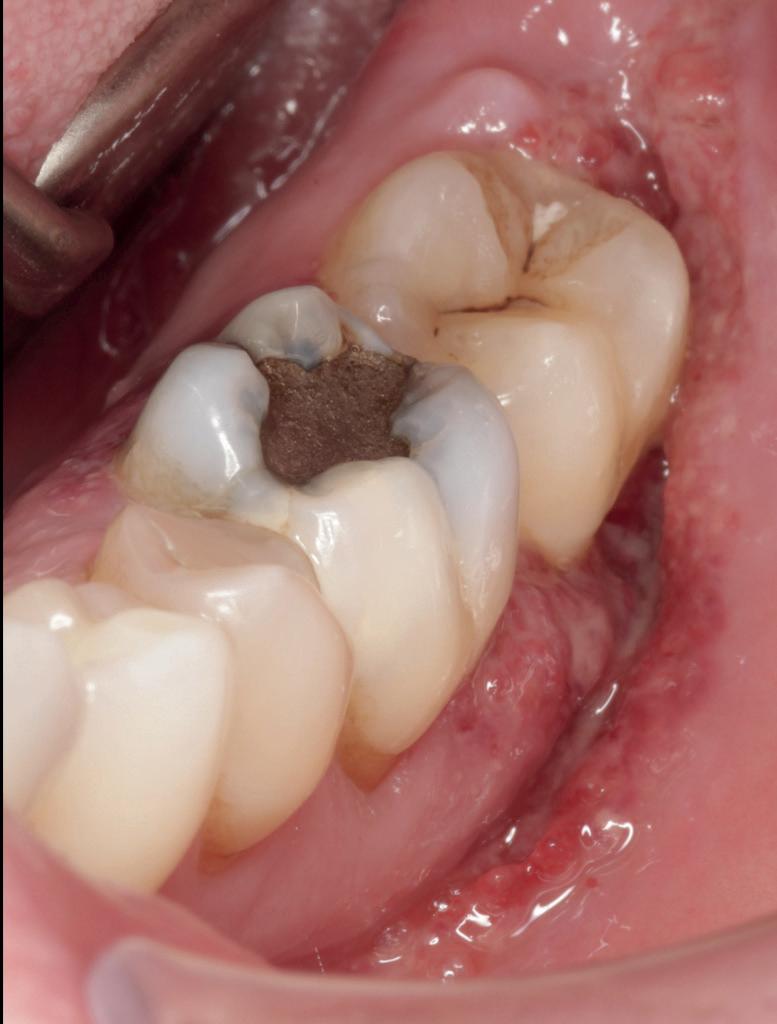

Nieuwe technieken, nieuwe risico’s

Vernieuwing is vaak een verbetering, maar niet in alle gevallen. Door de groffere oppervlaktestructuur van implantaten kunnen bacteriën zich makkelijker nestelen, met uitstoot van toxines tot gevolg. Dunne wanden van implantaten kunnen ervoor zorgen dat er vrije titaniumionen in de omgeving vrijkomen. De connectie van het implantaat met de suprastructuur kan bepalend zijn voor snel botverlies langs de rand van het implantaat.

Afhankelijk van het microbioom, de erfelijke belasting van de gastheer, de mondhygiëne en lifestylefactoren kunnen er allerlei problemen ontstaan rond de implantaten, met ontsteking van de omringende weefsels tot gevolg. Hoewel we steeds meer grip krijgen op deze situaties, is behandeling hiervan een grote uitdaging en zeker nog niet eenduidig (afbeelding 16-18).